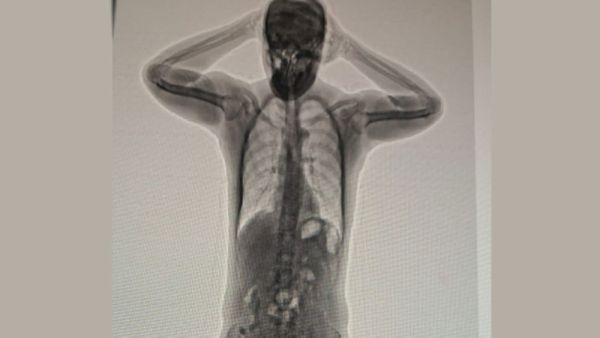

An expat was arrested for attempting to smuggle 50 capsules of heroin inside his body, the Royal Oman Police has announced.

According to the Royal Oman Police, “An Asian national was arrested on charges of possessing narcotic drugs for the purpose of trafficking. More than 50 capsules of heroin were found inside him.”